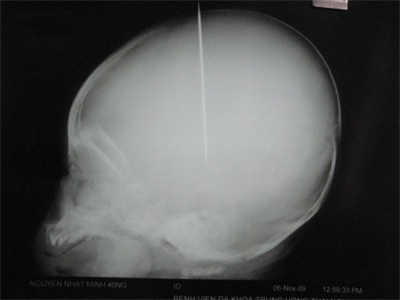

Chiếc kim khâu lốp đâm ngập trong đầu cháu bé.